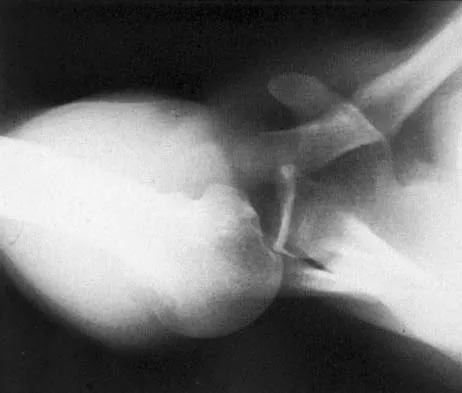

A 13-year-old boy has pain and a firm mass in his left knee. A radiograph and MRI scan are shown in Figures 2a and 2b, and a biopsy specimen is shown in Figure 2c. Based on these findings, what is the most likely diagnosis?

The most likely diagnosis is osteosarcoma. The imaging studies show an aggressive primary tumor of bone, and the histology slide shows a typical chondroblastic osteosarcoma, with osteoid deposited along the surface of bone trabeculae. Ewing's sarcoma histologically consists of small round blue cells. Osteochondroma and periosteal chondroma can occur near the knee but have different radiographic and histologic patterns. Chondrosarcoma rarely occurs in children. Simon M, Springfield D, et al: Osteogenic sarcoma: Surgery for Bone and Soft Tissue Tumors. Philadelphia, PA, Lippincott Raven, 1998, p 267.